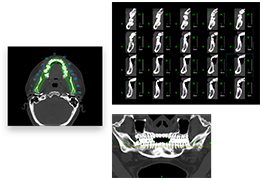

ART-Plan™ Artificial Intelligence Contouring